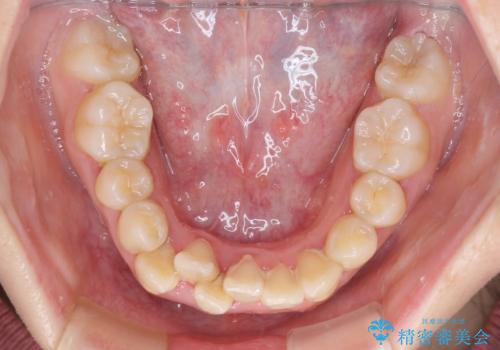

上下非接触で突出した前歯 ワイヤー装置による抜歯矯正

- 上下前歯の隙間と口元の出っ張った感じを気にして来院された患者様です。

上下の隙間は舌突出癖によるもので、またその癖により前歯が前方に出ている状態でした。

口元の出っ張りを改善するため、上下左右第一小臼歯4本を抜去し、ワイヤー装置にて矯正治療を行うこととしました。